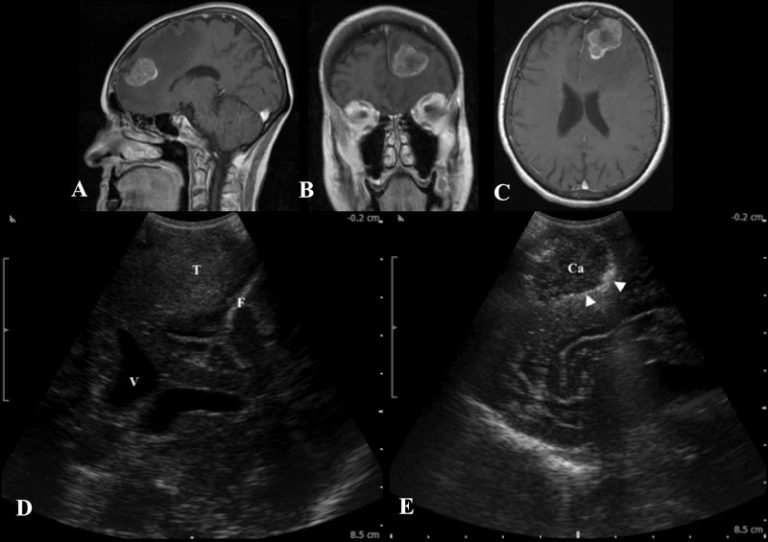

From njbrainspine.com

Intraoperative Ultrasound New Jersey Brain and Spine New Jersey Brain Cancer Cluster by meghan holohan. A new jersey high school is currently investigating a potential cancer cluster of. by donavyn coffey. More than 100 former students. cancer cluster probe at nj hs underway after 100+ diagnosed with brain tumors. an environmental assessment of all 28 acres in and around colonia high school found no traces of radiological. When. New Jersey Brain Cancer Cluster.